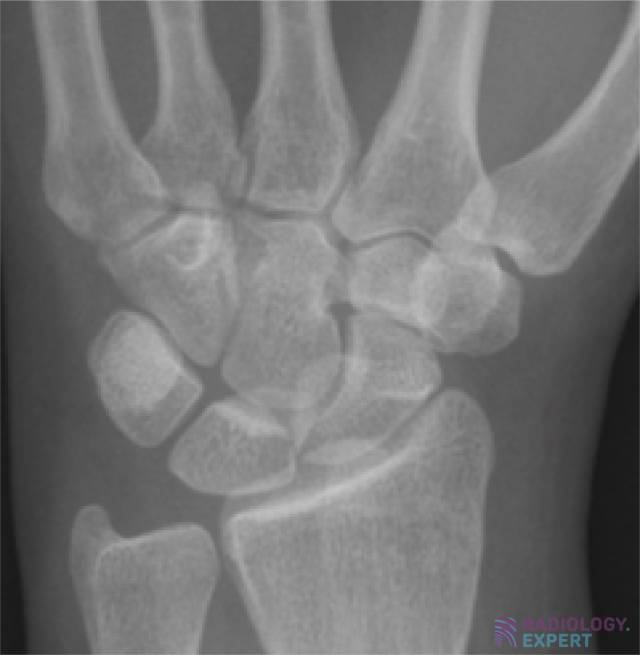

Carpal bones. Normal anatomy. Carpal bones. Normal anatomy.

Click image to see overlay